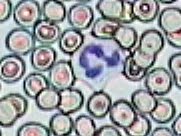

Práctica de Frotis sanguíneo 21